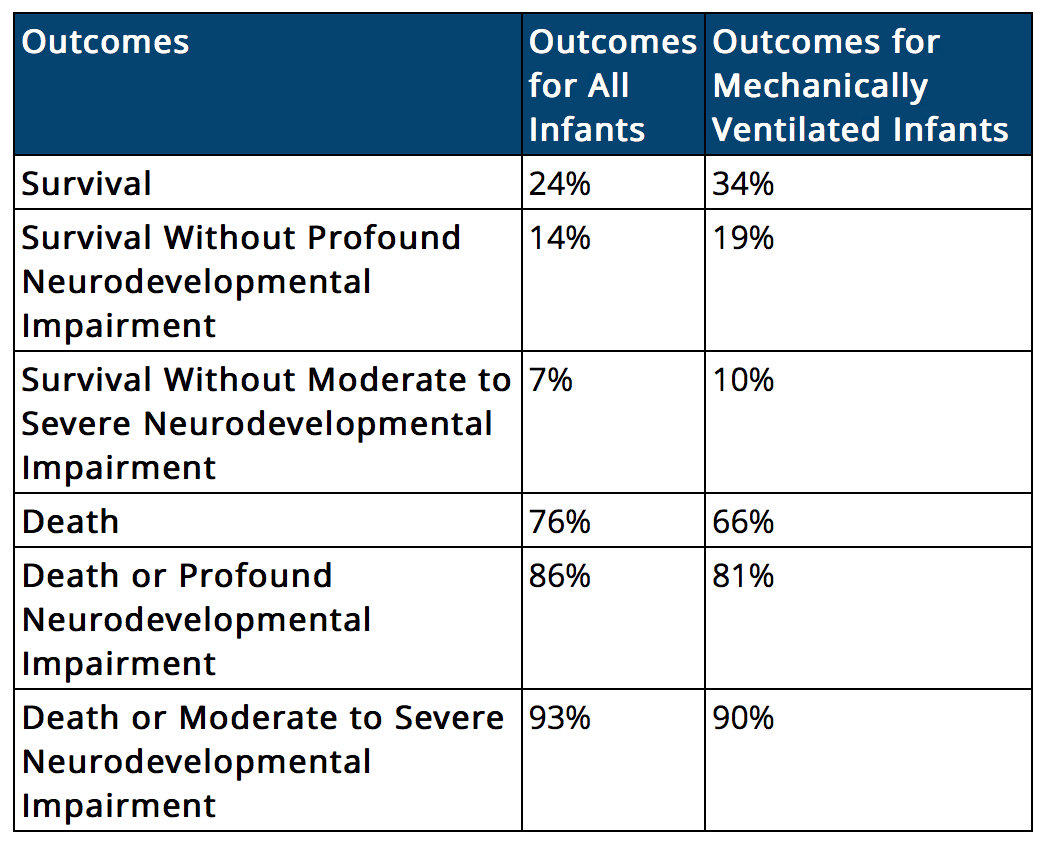

The night went on – 9pm, 10pm, 11pm – and sometime closing in on midnight, the neonatal doctor came in. My parents sat next to the bed, and Bjork was sitting just next to me, and the three of them were working hard to take in all the information from the doctor as he ran through a speech about what life is like for babies who are born at 23 weeks from his perch on a stool at the end of my bed. But I was not even trying. I was watching everything in the room happen around me – floating, emotionally gone, as words like “blindness” and “feeding tube” and “deaf” and “cerebral palsy” and “brain bleed” melted together and dissolved into a dull drone of syllables, hitting my ears but not being absorbed. Statistics. Survival rates. Consequences of extreme prematurity. I literally could not.

But 23 weeks? It is grey. It is ethics. It has been called one of the most agonizing decisions in medicine. It presents you with statistics like <30% survival and >90% disability. It is burning hell on earth for a brand new parent. We were right smack dab on the mark: 23 weeks and 0 days, which is both as close and as far as you could possibly be. At 23 weeks, doctors don’t assume. They ask you immediately upon arrival to the hospital: should we do everything possible to resuscitate your baby?